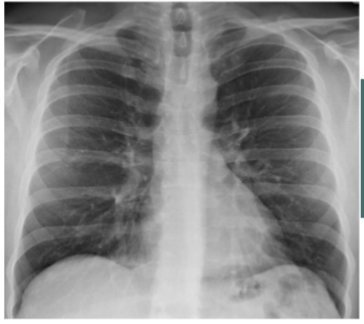

PA CXR

What is this

AP